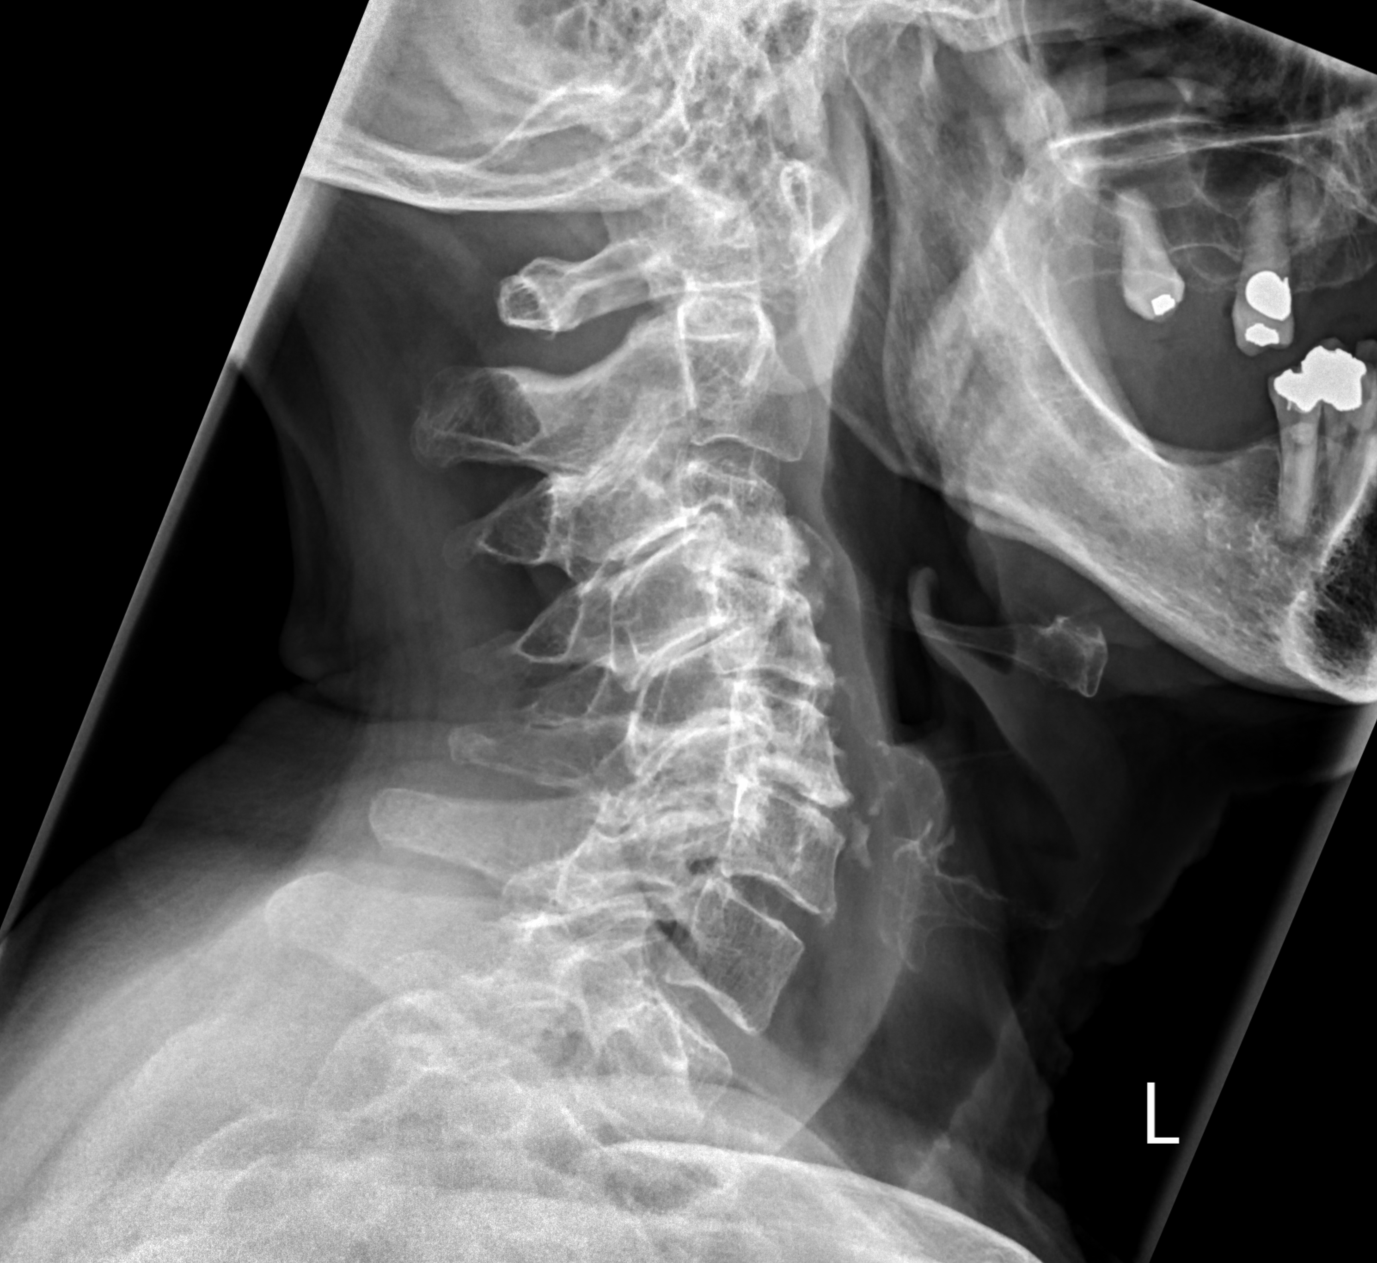

Atlantoaxial subluxation in polymyalgia rheumatica and rheumatoid arthritis Szerző: admin | jún 20, 2015 | MSK | Nincsenek hozzászólások The anterior arch of the atlas displaced 1 cm anterior to the odontoid due to pannus formation (calcified snovial proliferation). Known rheumatoid arthritis. another case of polymyalgia rheumatica